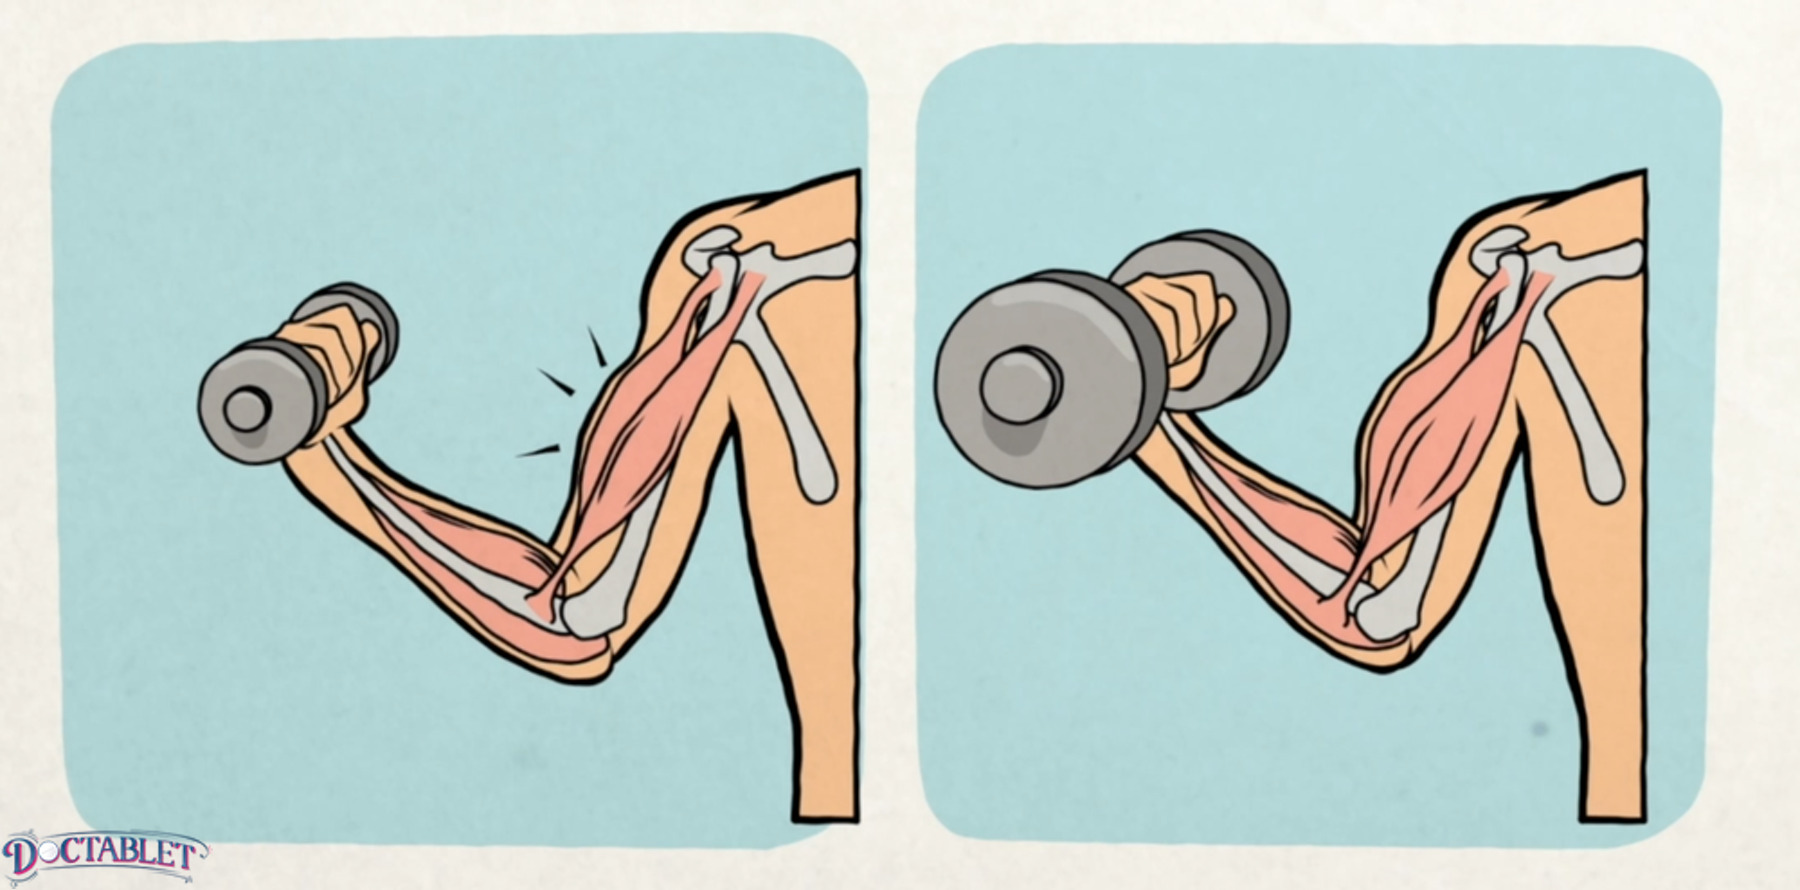

Two basic ways of exercising

Low-resistance, high-repetition exercises that build tone, endurance and strength. This is the type of exercise bikers and runners do.

Low repetition and high weight. This builds big muscles and increases the force of the muscle.

The heart can also become thick if it is exposed to the need to carry heavy weights. As the heart squeezes against the pressure generated by the arteries, we can think of blood pressure as the weight the heart is lifting. If blood pressure is high, this translates to the heart doing heavy bench presses every day. Over time, the muscle of the heart becomes thick like that of a bodybuilder. Thickening of the heart is a condition known as Left Ventricular Hypertrophy, or LVH for short. Cardiac hypertrophy is associated with a doubling of the chances of dying from a cardiac event. A thick and inflexible heart can also fail over time, causing a common complication known as heart failure. People who have thick hearts develop arrhythmias like atrial fibrillation much more often.